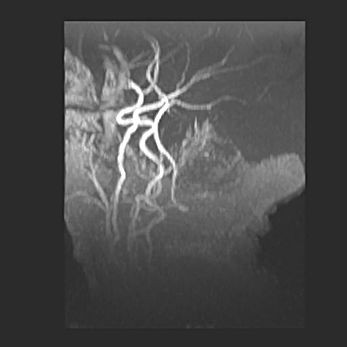

Церебральная ишемия II.

Возраст: 5 дней

Вес: 3400 г

Пол: женский

Окружность головы: 35 см

Срок гестации: 39 недель

Церебральная ишемия – это заболевание, характеризующееся недостаточностью (гипоксией) либо полным прекращением (аноксией) снабжения мозга кислородом по причине закупорки одного или нескольких сосудов. Это приводит к  что метаболическим расстройствам различной степени тяжести в тканях головного мозга, развитию коагуляционных некрозов и гибели нейронов.